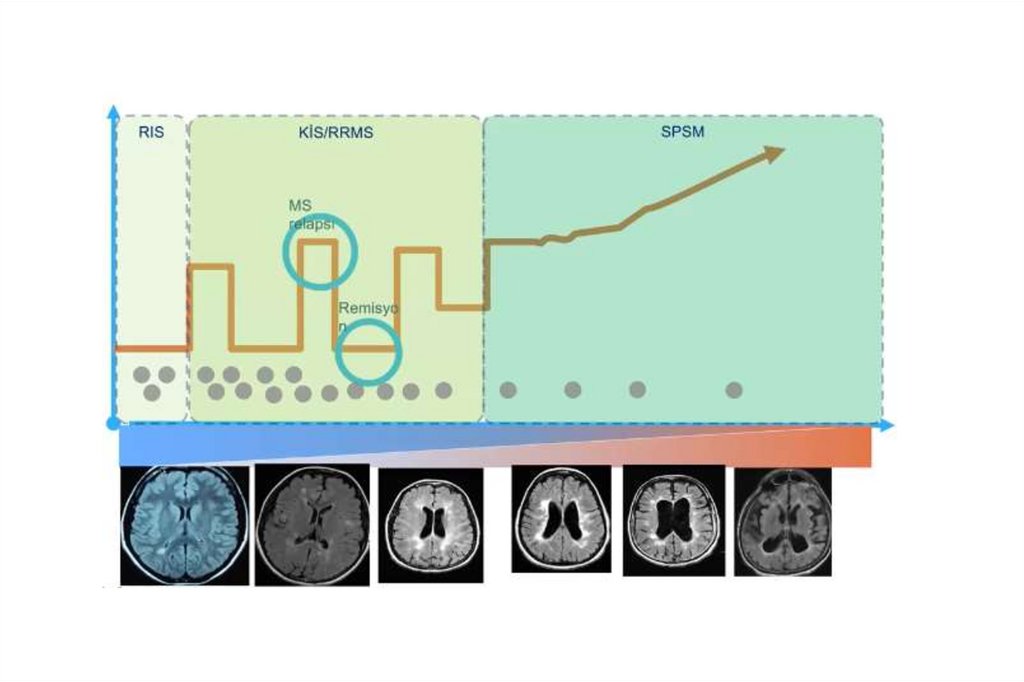

MS TİPLERİ

MS’te Aksonal Kesi

• MS’te klinik seyir, aksonal kayıp ve nörolojik özürlülük

arasındaki ilişki (!)

RR-MS=relapsing–remitting MS; SP-MS=secondary progressive MS.

Adapted from Trapp. Curr Opin Neurol. 1999;12:295.